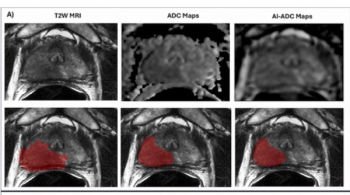

Emerging research showed that AI-generated ADC mapping from MRI led to significant increases in accuracy, PPV and specificity in comparison to conventional ADC mapping while achieving a 93 percent sensitivity for PCa.